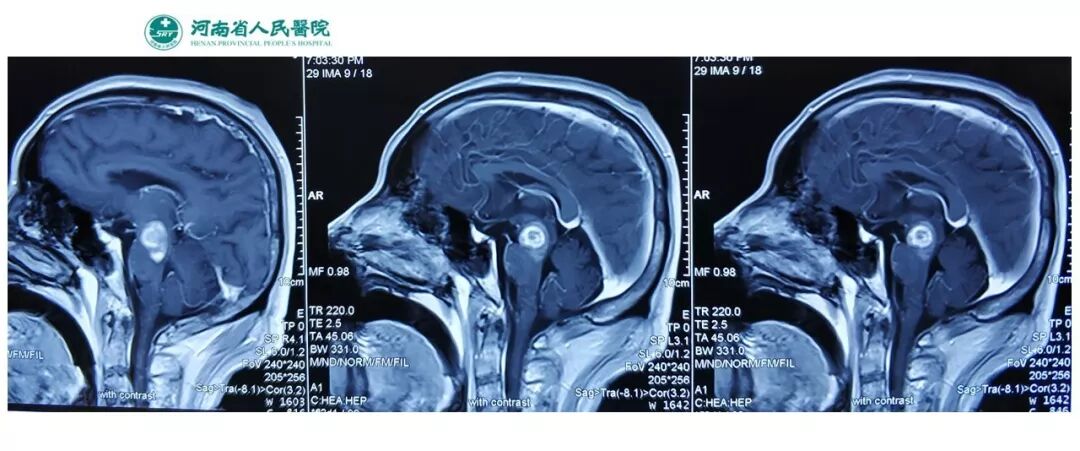

今天为大家分享的是《贝朗时间》第五十一期,由河南省人民医院神经外科步星耀教授团队带来的:脑干海绵状血管瘤伴出血手术病例分享,欢迎阅读、分享!